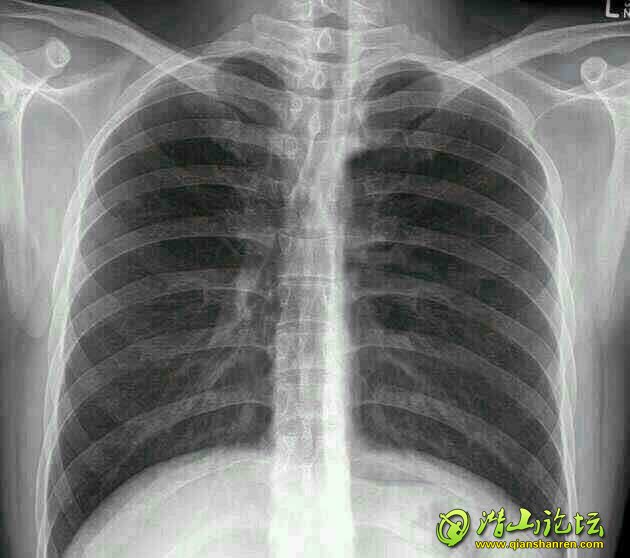

心内的博士,请读胸片一张:

39375741_看图王.jpg